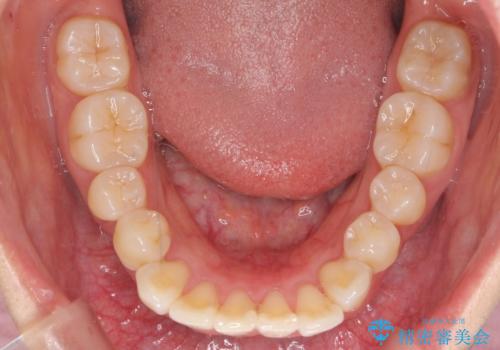

下の前歯を中に入れるためにIPR(歯をわずかに削る処置)を行いました。

左上の反対咬合になっていた歯の頬側咬頭は、すでに削れて短くなっていましたがそのまま並べています。